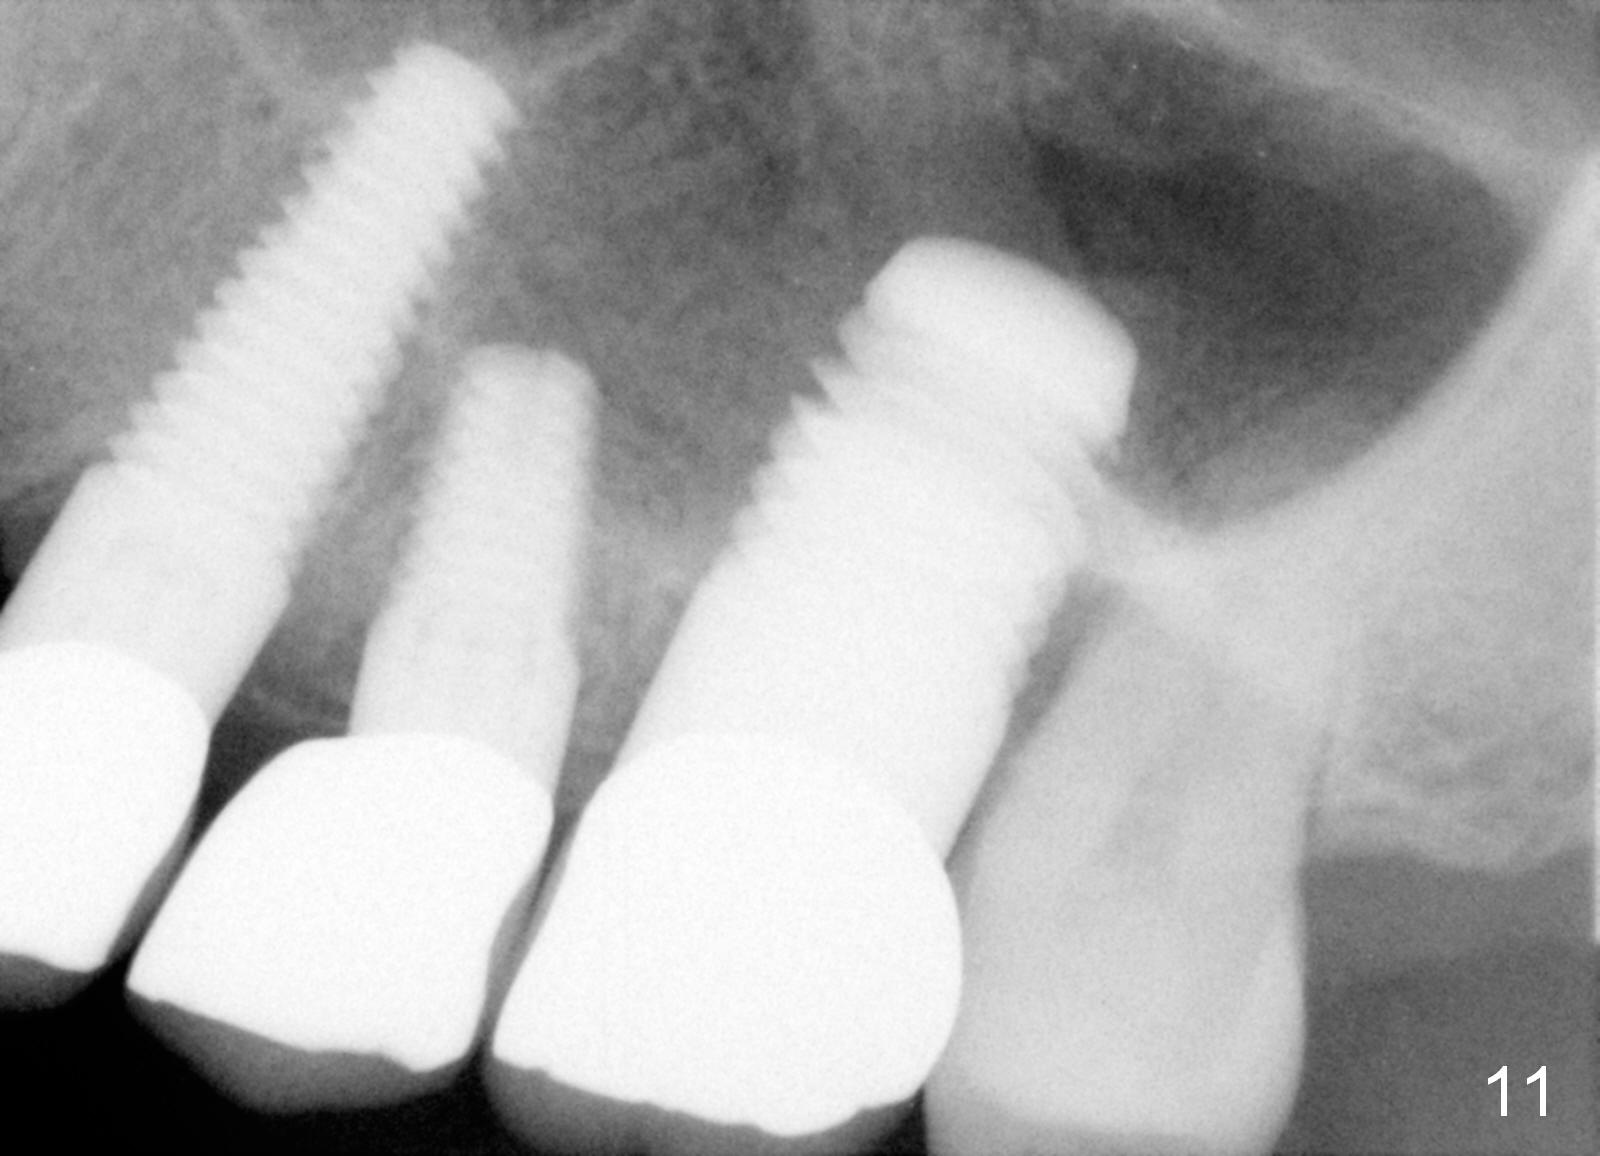

Anyway, three of the implants heal normally 3 months postop (Fig.10) and restore together. Fig.11 and 12 are taken 11 and 21 months post cementation.